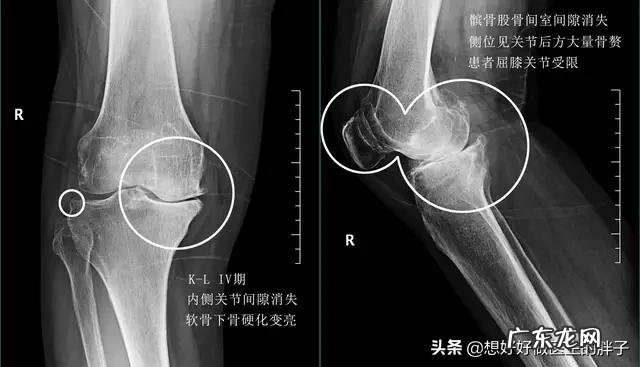

当关节软骨发生损害以后,关节表面变得不再光滑,反复的摩擦会增加骨关节的压力,同时由于关节的软骨的磨损,关节变得不再像以往那样稳定,我们的身体为了尽量维持关节的稳定,会用另外一种结构来弥补关节的不稳,那就是骨质增生,所以可以说骨质增生是一个比较好的结构,是来帮忙的,但是如果增生的太多刺激到了周边的软组织,导致患者出现疼痛,那就属于祸害了,此时我们称它为骨刺 。

当骨刺变得越来越多,患者的关节功能也就会越来越受到影响,严重的患者会出现难以忍受疼痛以及关节功能的障碍,不能正常的进行屈伸关节 。